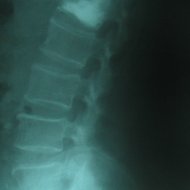

Kemik Erimesine (Osteoporoz) Bağlı Omurga Kırığı: İleri yaşta osteoporoz, yaşlılık ve/veya menopoza bağlı kemik kitlesinin azalması nedeniyle oluşur. Kemikleri zayıflatan bu sorun nedeniyle basit travmalarda bile kemikler kırılabilir hale gelir. En çok kırılan kemikler omurga ve kalça kemikleridir. Osteoporozun çok ileri olduğu bazı durumlarda hasta aksırınca bile omurgası kırılabilir. Bu durumda hastaya kemik çimentosuyla dolgu tekniği (vertebroplasti) uygulanabilir. Ancak tekrarlayabileceği göz önünde bulundurularak kemik erimesine yönelik ilaç tedavisi unutulmamalıdır. Hastalarda en sık ortaya çıkan şikayet sırt ya da bel ağrısıdır. Bazen çökme kırıkları sonucu olan ağrı hastayı çok rahatsız etmez ama oluşan deformite sonucu hasta doktora başvurur. Yaşlılarda Kifoz: Yaşlanan omurgada hem osteoporotik kırıklar hem de disklerde oluşan dejenerasyonla beraber kifoz oluşabilir. Bu durum bir yandan hastada solunum sorunları oluştururken diğer yandan günlük aktiviteleri kısıtlar. Yaşlılarda Skolyoz: İleri yaşta skolyoz ya dejeneratif omurga sorunları sonucunda ya da geçmişte var olan skolyozun artmasıyla oluşabilir. Birinci durum sinirlere bası nedeniyle sıklıkla bacaklara yayılan ağrı ile beraberdir.

Kemik erimesine (osteoporoza) bağlı omurga kırığı olan hastada vertebroplasti (çimento ile dolgu) tedavisi